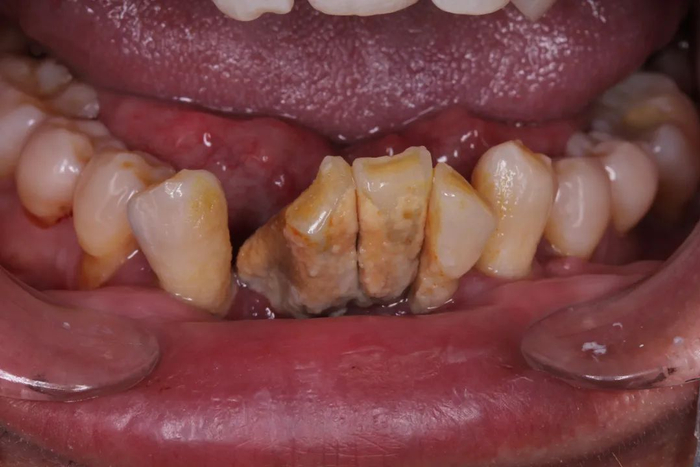

大量牙结石,导致牙齿松动移位,

再再后来,牙齿不仅仅松动了,它们可能还开始移动位置了——牙齿和牙齿之间的缝隙越来越大。而之前松动的牙齿开始摇摇晃晃,有的还会出现牙齿的疼痛!

这时候再不看牙,光想着吃点药止一下痛,其实已经开始无济于事了。牙根开始暴露出来,牙齿的松动越来越严重。

直到某一天,这个摇摇欲坠的牙齿寿终正寝,正式离开口腔,光荣殉职。